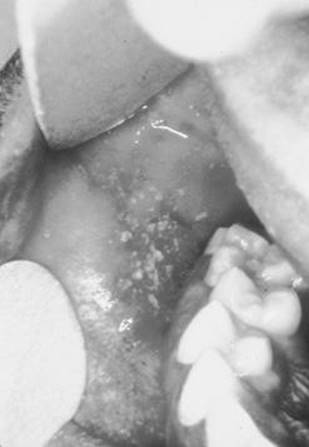

Koplik spots (pathognomonic): Irregularly shaped spots with grayish white centers on buccal mucosa (see Figure 10-2).

FIGURE 10-2. Koplik spots (rubeola).

(Reproduced, with permission, from Knoop KJ, Stack LB, and Storrow AB. Atlas of Emergency Medicine, 1st ed. New York: McGraw-Hill, 1997: 174.)